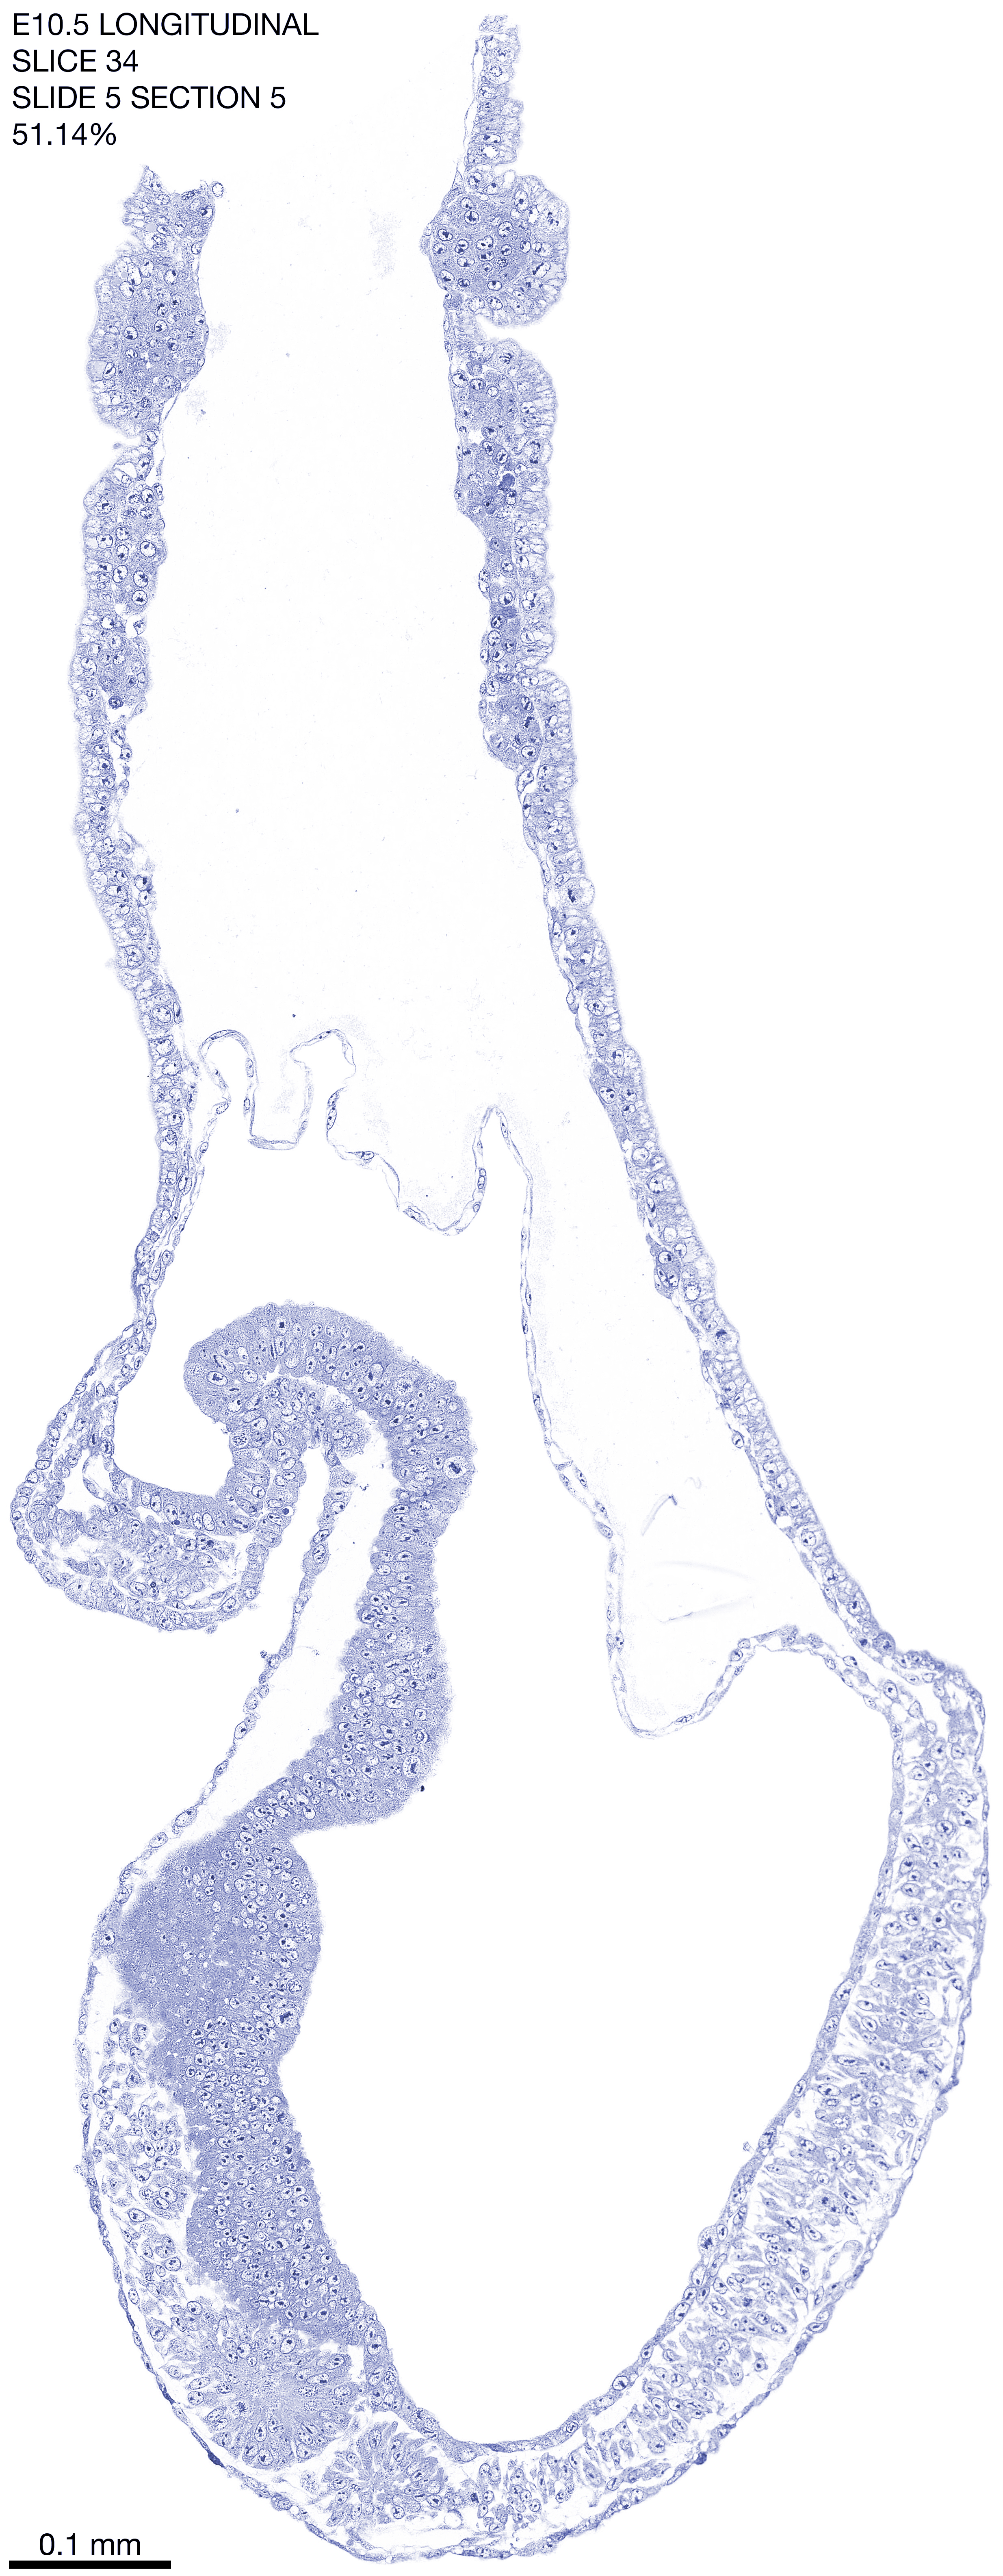

E10.5 Longitudianal Archive This page contains jpg files of ALL SLICES (each 3µm thick) that were scanned of the E10.5 longitudinally cut specimen. Download: Large | High Res Download: Large | High Res Download: Large | High Res Download: Large | High Res Download: Large | High Res Download: Large | High Res Download: Large | High Res Download: Large | High Res Download: Large | High Res Download: Large | High Res Download: Large | High Res Download: Large | High Res Download: Large | High Res Download: Large | High Res Download: Large | High Res Download: Large | High Res Download: Large | High Res Download: Large | High Res Download: Large | High Res Download: Large | High Res Download: Large | High Res Download: Large | High Res Download: Large | High Res Download: Large | High Res Download: Large | High Res Download: Large | High Res Download: Large | High Res Download: Large | High Res Download: Large | High Res Download: Large | High Res Download: Large | High Res Download: Large | High Res Download: Large | High Res Download: Large | High Res Download: Large | High Res Download: Large | High Res Download: Large | High Res Download: Large | High Res Download: Large | High Res Download: Large | High Res Download: Large | High Res Download: Large | High Res Download: Large | High Res Download: Large | High Res Download: Large | High Res Download: Large | High Res Download: Large | High Res Download: Large | High Res Download: Large | High Res Download: Large | High Res Download: Large | High Res Download: Large | High Res Download: Large | High Res Download: Large | High Res Download: Large | High Res Download: Large | High Res Download: Large | High Res Download: Large | High Res